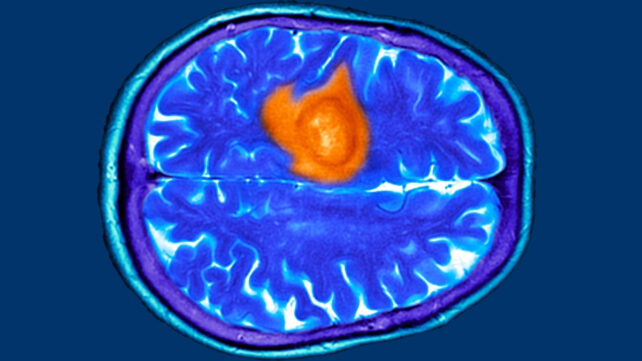

Yet they're also examples of symptoms that can, in rare cases, signal something far more serious: a brain tumour.

Brain tumour symptoms often resemble everyday experiences – tiredness, stress, migraines, or menopause – and overlap with much more common conditions such as anxiety, sinus infections, or chronic headaches.